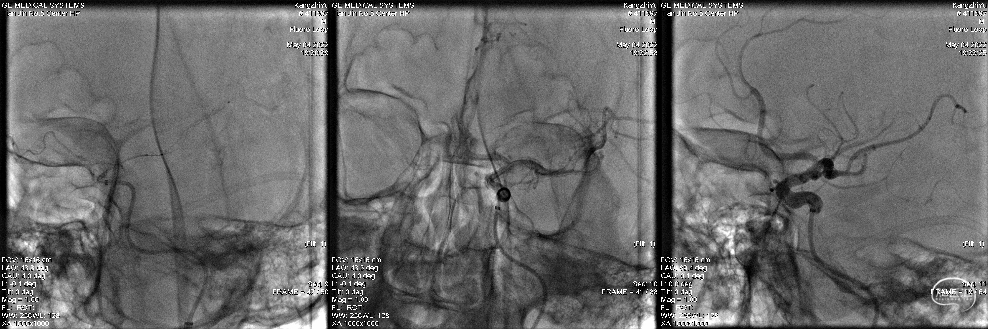

急诊行脑血管造影

左侧大脑中动脉M2段分支闭塞。

导丝导引下将微导管置于大脑中动脉M2段远端冒烟确认。

到位后释放支架,Trevo XP取栓支架,全程可视,有效判断病变性质,无动脉原位狭窄;见M2段血流恢复,应用“SWIM”技术,支架释放后,中间导管高到位,支架回撤取出少量血栓,复查造影见M2段远端显影仍欠佳,考虑血栓逃逸。

微导丝导引下将pro18微导管置于大脑中动脉M2段以远,冒烟确认后,再次释放支架,支架全节段显影,初步判断无原位狭窄。重复标准“SWIM技术”取栓,取出少量斑块。

复查造影见各级血管通畅。